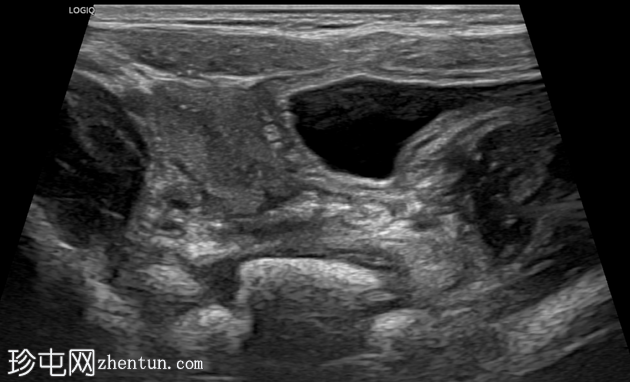

横切面

纵切面

右侧努克氏疝管长约6毫米,内含部分子宫和卵巢(大小约1.5 x 1厘米)。在整个检查过程中,这些组织均保持原位。

对侧附件呈多囊性改变,大小约3 x 1.8厘米。

膀胱外观大致正常。

上述超声特征清晰地显示了努克氏疝管的内容物及其延伸范围;其中包含患者的一侧卵巢和部分子宫组织。

这些特征符合卵巢努克氏疝的诊断。